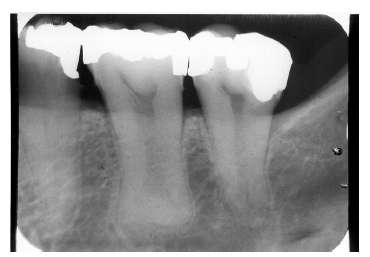

In Figure 4, recurrent caries appears at the mesial of tooth #3 and #4, and the distal of tooth #28. Also, note areas of interproximal caries on teeth #5-6.

Figure 4 - Recurrent Caries

Figure 4